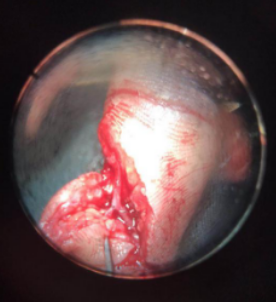

术中探查血管是在指尖血管分叉以远断裂,分别给予吻合两个分支动脉血管及掌侧2根静脉,动脉的血管管径仅有0.2mm.

唐洪伟医生说:这个手术难度比较大,令人头疼。主要是血管太细,不容易找到,找到以后,需要非常高的显微外科技术,可能很多人一看这种情况,就直接放弃再植手术了。还有患者求医心切,内心非常紧张,术后血管容易痉挛,影响术后成活,同时也面临着万一不成话,还需要二次手术等心理压力,不过看着病人,对我信任的眼神和殷切的希望,我还是决定立即行再植手术。现在患者手术成功,功能正常,手指活动非常灵活,非常满意。